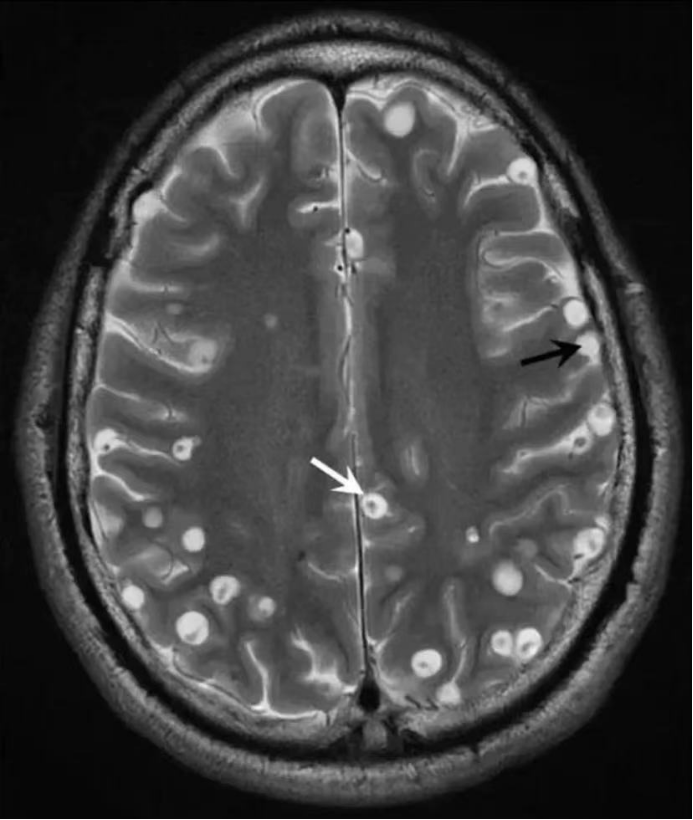

鲁先生因左下肢抽搐1周

到普洱市中心医院

影像学检查显示如下:

就是鲁先生诊断为脑囊虫病

脑囊虫病是由寄生虫(猪绦虫为主)所传染的一种顽固性颅脑内疾病。该病约占囊虫病的80%以上。是由于食用了猪肉绦虫虫卵,发育成囊尾蚴,经消化道穿出肠壁进入肠系膜小静脉,再经体循环而到达脑膜、脑实质以及脑室内。